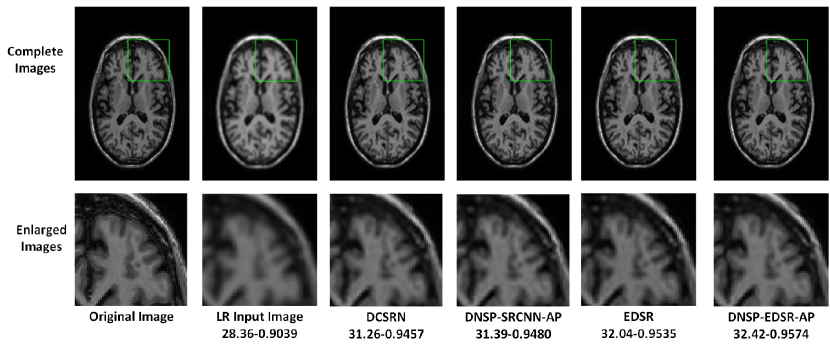

Figure 13: Comparisons of top 4 methods for an image in ADNI dataset for scale factor of 4. A small portion of the images (marked by green box) in the first row is zoomed in and shown in second row. The numerical figures constitute the respective PSNR-SSIM values.

Table II shows PSNR and SSIM values for all competing methods. Note that we used two different base networks for DNSP: 1) DNSP-SRCNN-AP - the base network is SRCNN and 2) DNSP-EDSR-AP - the base network is EDSR. Three trends emerge from the results: 1) DNSP-EDSR-AP outperforms the competition, 2) DNSP-SRCNN-AP does better than all the methods except EDSR, and 3) overall, deep SR methods, i.e. SRCNN, EDSR, DCSRN and DNSP perform better than other alternatives. To confirm this statistically, we performed a 2-way Analysis of Variance (ANOVA) on PSNR values for all the methods across the two datasets which is illustrated in Fig. 10. It may be inferred from Fig. 10 that deep learning methods are statistically well separated from the traditional methods and further DNSP-EDSR-AP is well separated from all the competing methods indicating the effectiveness of using prior information. Figures 11 and 12 illustrate the results of the top 4 methods w.r.t. PSNR on a sample image from BW and ADNI databases respectively for a down-sampling factor of 2 while Figures 13 and 14 show results for a down-sampling factor of 4. DNSP-EDSR-AP particularly excels in recovering fine image detail (enlarged with zoom-in boxes), thanks to data-adaptive sharpness.